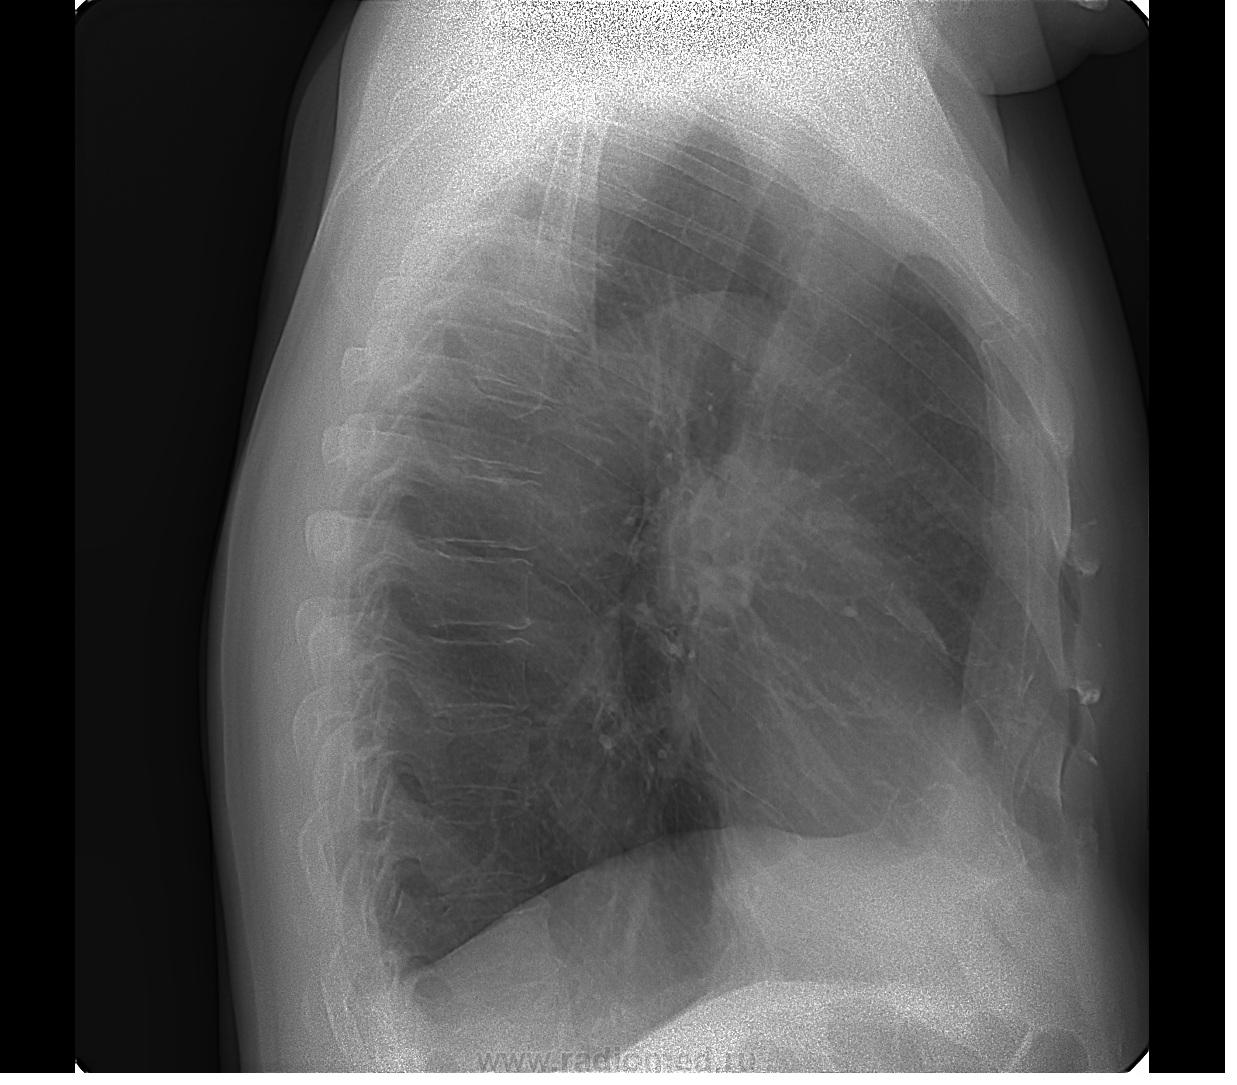

В лёгких очаговых и инфильтративных изменений не нахожу. Справа плевроперикардиальная спайка. Cor в норме. Слева состояние после прелома IX ребра в области наружной дуги.

Дополнительно. Справа на уровне 5-6 ребер линейная спайка вдоль костальной плевры. Слева - звездчатое образование в проекции 4-5, думаю, что сосудистое.

серъезные вещи пишут )на рентгнограммах правая половина диафрагмы на уровне 11 ребра ,что косвенно говорит об обструкции ,а так сделайте кт ,а потом ясно будет

Еще что-нибудь, говорите? - конечно! Не увидела ничего, пока автор не показал. За тенью рукоятки грудины есть дополнительная тень, накладывающаяся на позвоночник в боковой проекции. ИМХО)

думаю там в боковой проекции сегмент первий ателектаз начинается

Са верхней доли правого легкого. Всем спс.

По снимку перелом VIII ребра, а не IX...

На мой взгляд, то, что накладывается на позвоночник, уж никак на рак не похоже.

А, купол диафрагмы справа не смущает?